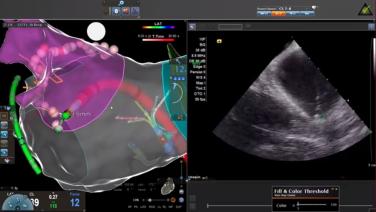

Creating an Accurate Left Atrial Map During the AF Procedure with Brett Gidney, MD

Catheter Manipulation & Clinical Considerations During the AF Procedure with Brett Gidney, MD